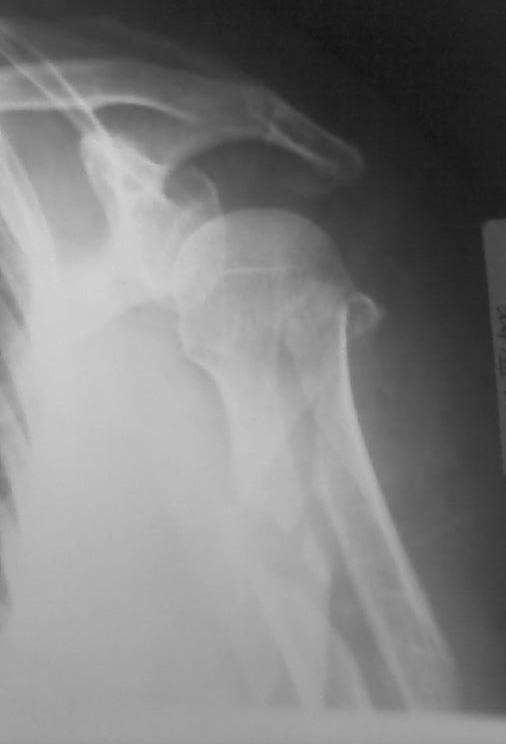

Уважаемый коллега! для закртытого БИОС данное стояние отломков вполне приемлемое, но импиджмент неизбежен. С уважением Ерсин Жунусов.

Высылаю рентгенограммы больной до операции и в гипсовой лонгете. Сейчас больную вообщем-то особо ничего не беспокоит, незначительная болезненность в области перелома при движениях плечом, первые два дня была отечность кисти, которая сейчас исчезла, объем движений в локтевом суставе постепенно увеличивается, отведение плеча пока небольшое. Дистальное блокирование выполнено одним винтом в передне-заднем направлении (через бицепс. Да, клинок мы конечно же заблокировали концевым колпачком. Нас тоже беспокоит возможность развития импиджмент синдрома, надеемся на то, что больная разработает движения в плечевом суставе.